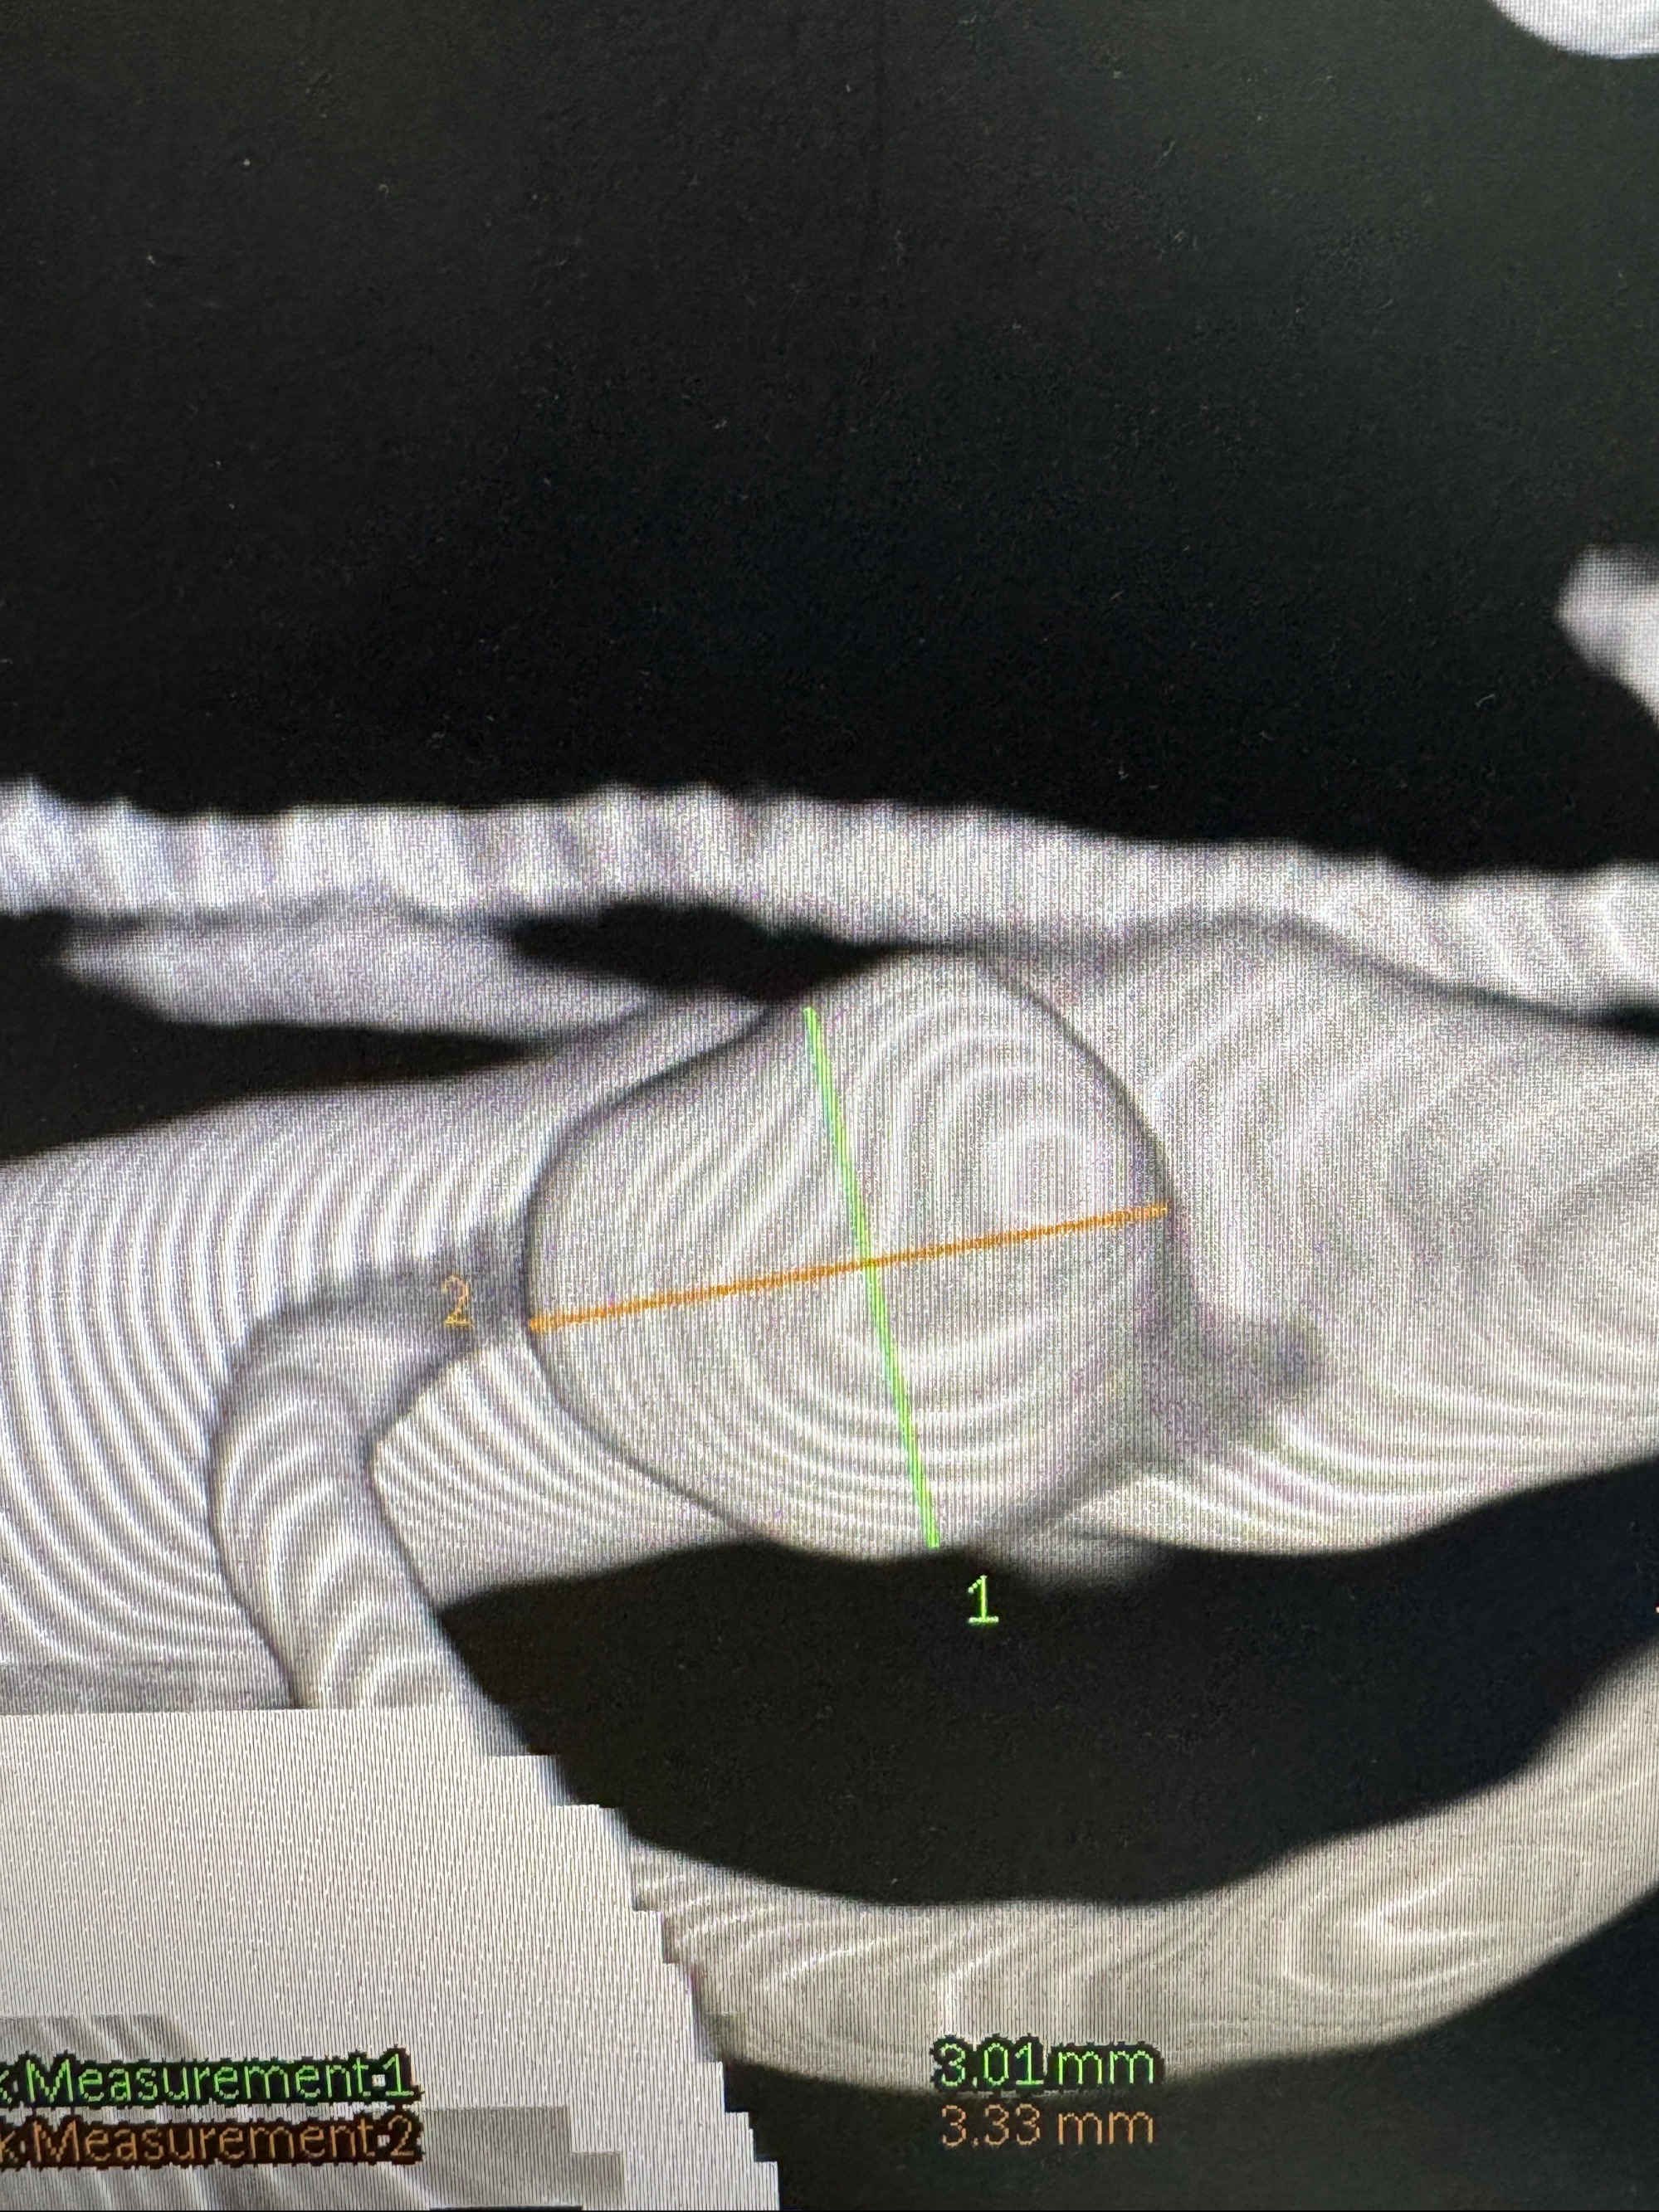

2023-06-26 安徽省立医院 头颅CTA:右侧大脑中动脉M1段动脉瘤,双侧颈内动脉虹吸段管壁钙化斑块,管腔无明显狭窄,双侧大脑中动脉M1段管腔狭窄;

2023-10-25 安徽省立医院 头颈部CTA:右侧大脑中动脉M1段动脉圆锥,主动脉弓混合斑块,双侧颈内动脉虹吸部钙化斑块,双侧大脑中动脉M1段硬化性狭窄,多灶性脑梗塞,老年脑改变;

2023-11-24DSA:右侧大脑中动脉下干起始部动脉瘤,约2.3*2.5mm,形态规则